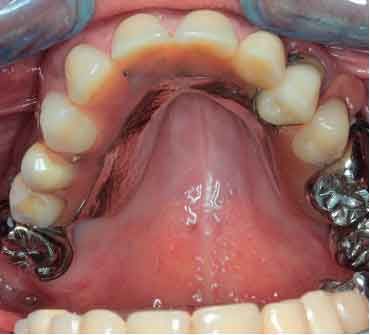

Picture - Initial bite situation

3D models - Bite scan from intra-oral scanner